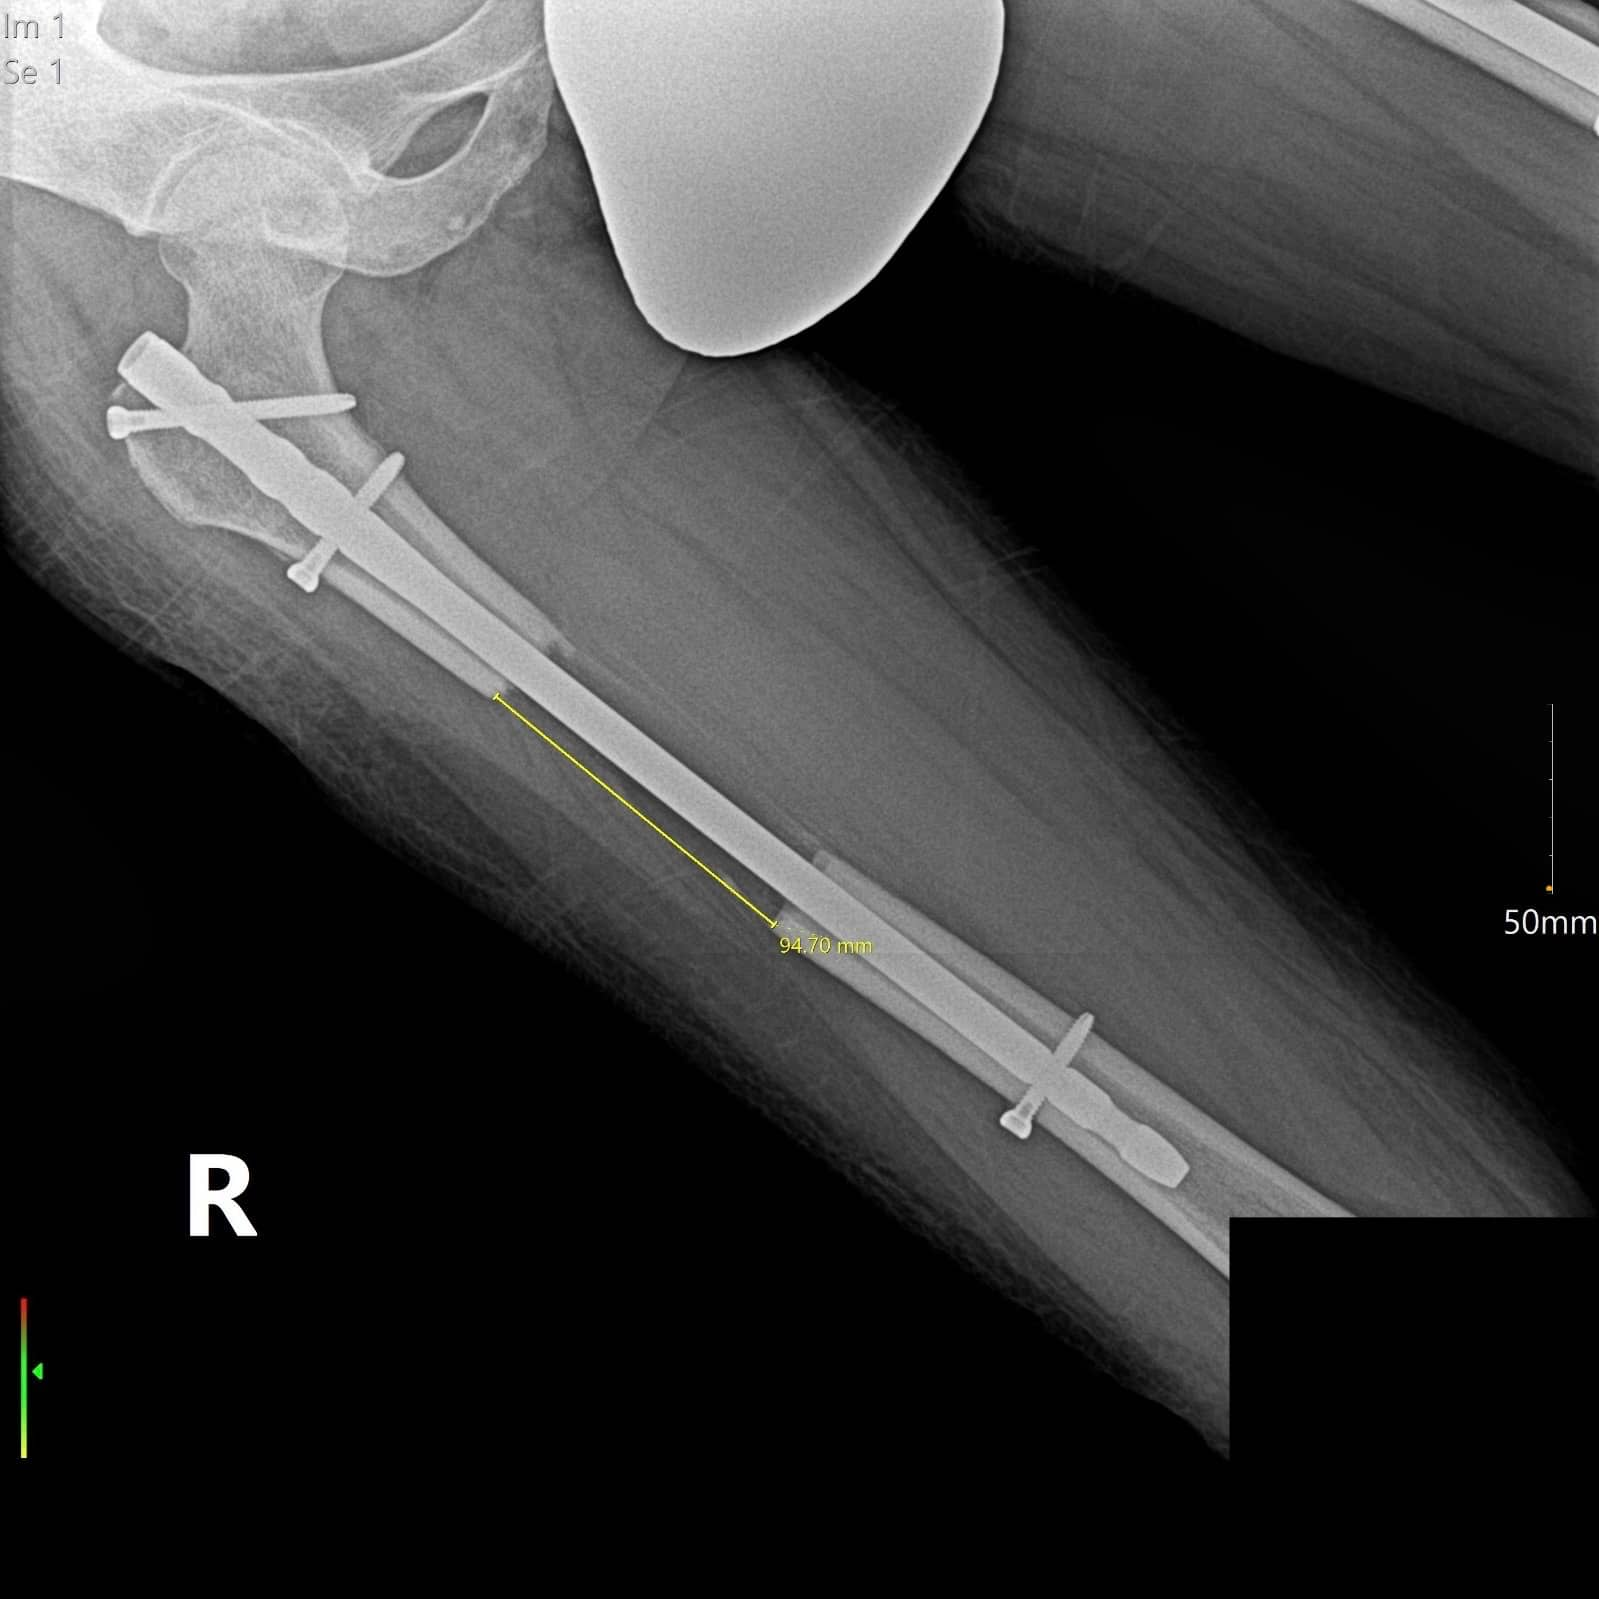

The lengthening over nail starts 5 days after surgery if you have the femur lengthening. For the tibia lengthening, the patient starts lengthening 7 days after surgery. The start of the lengthening may vary depending on the situation of the patient.

After discharging from the hospital, the lengthening phase starts. Throughout the limb lengthening process, it is essential for the patient to undergo physical therapy and receive expert medical support. For example, with an 8 cm target extension (1 mm per day extension), the patient is finished with the complete extension in 80 days.

The recovery timeline depends on how many centimeters the bone is lengthened. On average, the external fixator is removed a few weeks after the desired length is reached, while the internal nail remains until the new bone fully heals. Follow-up visits and X-rays are required during the healing phase to ensure the bone is forming correctly.

After the LON method surgery, the patient starts lengthening approximately 5-7 days later. Following this, physiotherapy sessions commence, accompanied by doctor visits every 2 weeks, and X-Rays taken every 10-15 days. These steps enable the doctor to measure the extent of the lengthening and provide an assessment. Once patients reach their targeted goal, the removal process takes place, initiating the subsequent recovery phase.